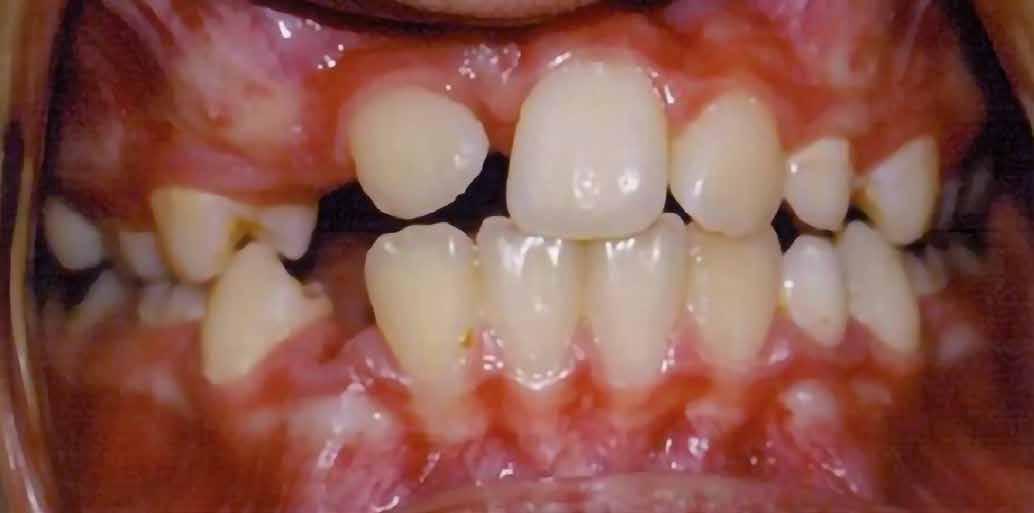

A vegyes fogazati kezelési célok a fogívek tágítása és a mandibula meziális irányú növekedésének a biztosítása volt. Fontos, hogy az ilyen típusú készülékeket nem csak éjszaka, hanem napközben is – amennyit csak lehet – hordani kell a minél hatékonyabb működés érdekében. A 18 hónapos első fázisú kezelésnek köszönhetően az alap kezelési célok megvalósultak, sikerült a class 1-es okklúziót beállítani (4-7. képek).

terséges harapásemelés pedig az alsó hatosokra, majd később a felső négyesekre került (8. kép). Az intermaxilláris elasztikus gumihúzás class-2-ess vektorú volt annak érdekében, hogy a disztálharapás korrekciója tökéletes legyen (9. kép). A harapást beállító elasztikus gumihúzásokat – mint minden kezelésnél –, ebben az esetben is folyamatosan, az egész kezelés alatt 24 órában (étkezések kivételével) viselte páciensünk.

A második Pitts-21 fix készülékes fázis ideje 16 hónap volt (10-12. képek)